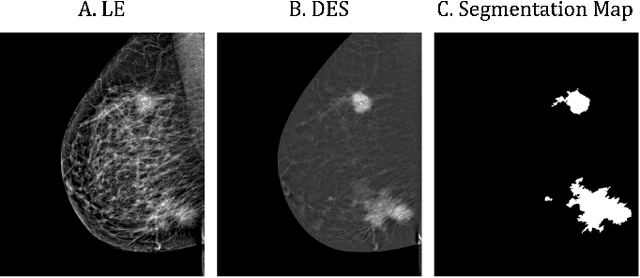

Abstract:Contrast-Enhanced Spectral Mammography (CESM) is a dual-energy mammographic technique that improves lesion visibility through the administration of an iodinated contrast agent. It acquires both a low-energy image, comparable to standard mammography, and a high-energy image, which are then combined to produce a dual-energy subtracted image highlighting lesion contrast enhancement. While CESM offers superior diagnostic accuracy compared to standard mammography, its use entails higher radiation exposure and potential side effects associated with the contrast medium. To address these limitations, we propose Seg-CycleGAN, a generative deep learning framework for Virtual Contrast Enhancement in CESM. The model synthesizes high-fidelity dual-energy subtracted images from low-energy images, leveraging lesion segmentation maps to guide the generative process and improve lesion reconstruction. Building upon the standard CycleGAN architecture, Seg-CycleGAN introduces localized loss terms focused on lesion areas, enhancing the synthesis of diagnostically relevant regions. Experiments on the CESM@UCBM dataset demonstrate that Seg-CycleGAN outperforms the baseline in terms of PSNR and SSIM, while maintaining competitive MSE and VIF. Qualitative evaluations further confirm improved lesion fidelity in the generated images. These results suggest that segmentation-aware generative models offer a viable pathway toward contrast-free CESM alternatives.